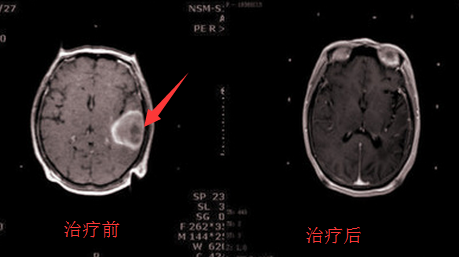

左颞叶脑胶质瘤治疗前后

临床研究已证实:采用WB-1全身热疗+rAd-基因,包括头颈部肿瘤、皮肤癌、宫颈癌、肺癌、胃癌、肠癌、食道癌、胆囊癌、卵巢癌、脂肪肉瘤、横纹肌肉瘤、复发性甲状腺癌和胸腹腔转移癌等。32%的病人肿瘤完全消退(CR),27%的病人肿瘤部分消退(PR),41%病人肿瘤停止生长(SD)。在美国、加拿大、日本和欧洲的30多个医学中心联合化疗或放疗治疗复发性晚期癌症病人,其疗效高于单纯放疗、化疗疗效3倍,没有毒副作用。